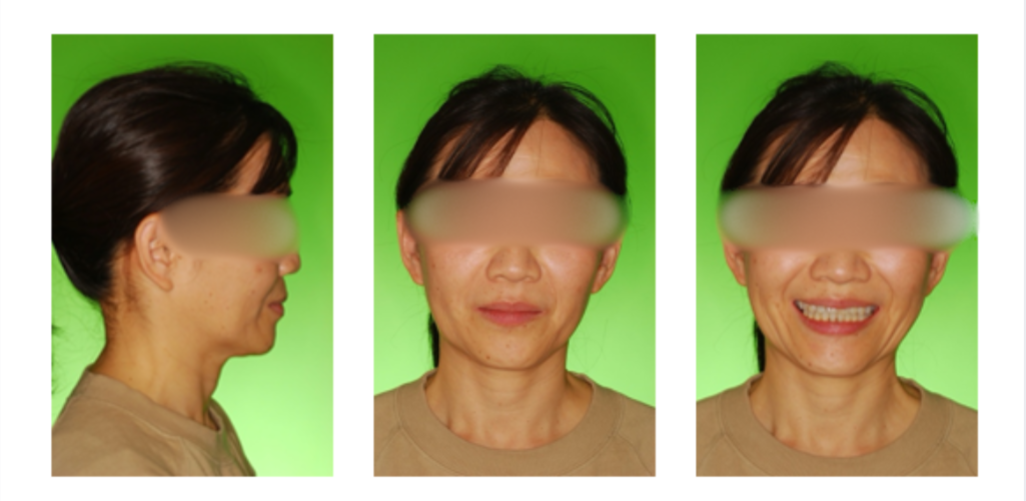

過蓋咬合の症例

初診時

治療終了時

治療終了から2年経過時

(保定開始から2年経過時)

初診

治療終了時

治療終了後から2年経過時

(保定開始時から2年経過時)

| 年齢・性別 |

20代 女性 |

| 主訴 |

前歯の隙間を治したい。咬み合わせが深いのが気になる。 |

| 治療について |

咬み合わせを改善するため、 上顎の前歯を圧下し、後退させるようにコントロールを行いました。 |

| 注意点・リスク |

矯正治療中に顎の位置が不安定になり易く顎関節症を発症する可能性が高くなります。また、歯牙移動に伴う痛み、発音し難くなったり、咬み難さが生じることがあります。歯根吸収(歯の根が短くなる状態)、歯髄壊死(歯の神経が失活した状態)、歯肉退縮(歯茎が下がる状態)、骨性癒着(骨と歯が癒着し、歯が動かない状態)が起きる可能性があります。 |

| 治療期間 |

1年3ヶ月 |

| 治療費用 |

718,900円(検査料と診断料で42,000円) |

| 治療に用いた主な装置 |

マルチブラケット装置(表側の装置) |

| 抜歯部位 |

上下顎両側第三大臼歯(予定) |

| 通院回数 | 14回 |

後戻りがほぼなく、長期的に歯並び、咬み合わせが安定しています。